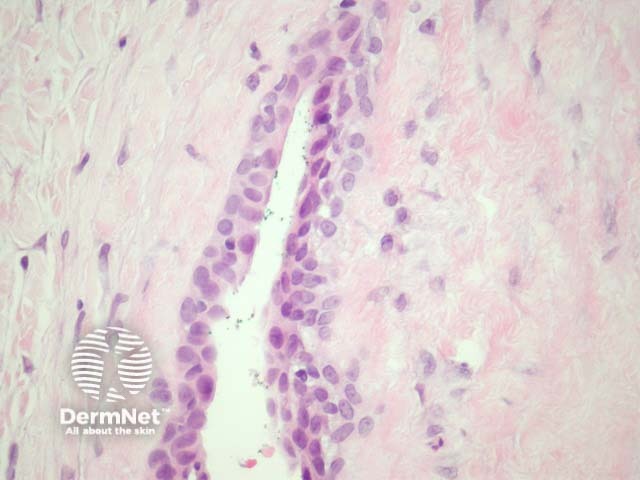

The lining of the cyst is usually a pseudostratified columnar epithelium (figure 2). Some cases may have mucinous glandular epithelium (figure 3) or a mixture of mucinous, transitional, and squamous epithelia. Cilia are usually not seen. At times, the lining epithelium may be entirely denuded.

Figure 3